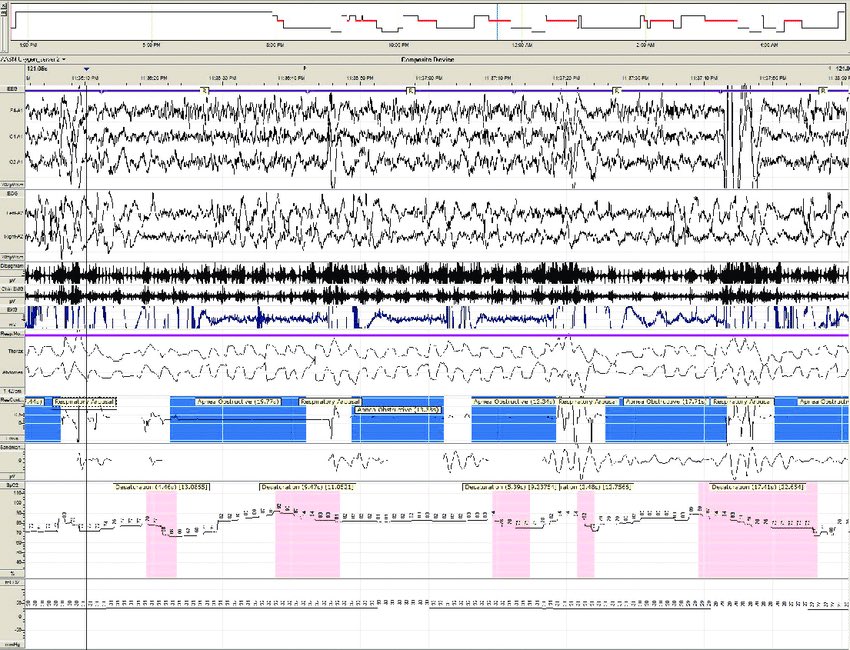

"انقطاع النفس الانسدادي النومي" OSA

وهو حالة توقف التنفس جزئيا او كليا لمدة تزيد عن ١٠ ثواني أثناء النوم يصاحبها نقص الاكسجين في الدم ومن ثم يقضة الدماغ المتكرر.